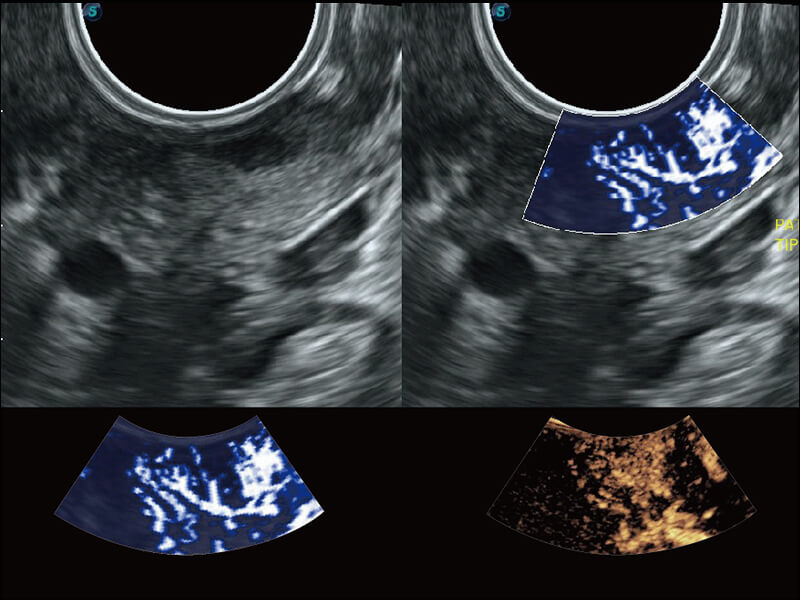

S60创新的探头工艺、高精度模数转换系统、前沿的波束重建技术,从前端信号处理每一个环节采集无损声学数据,真实还原组织原貌,再现解剖细节。